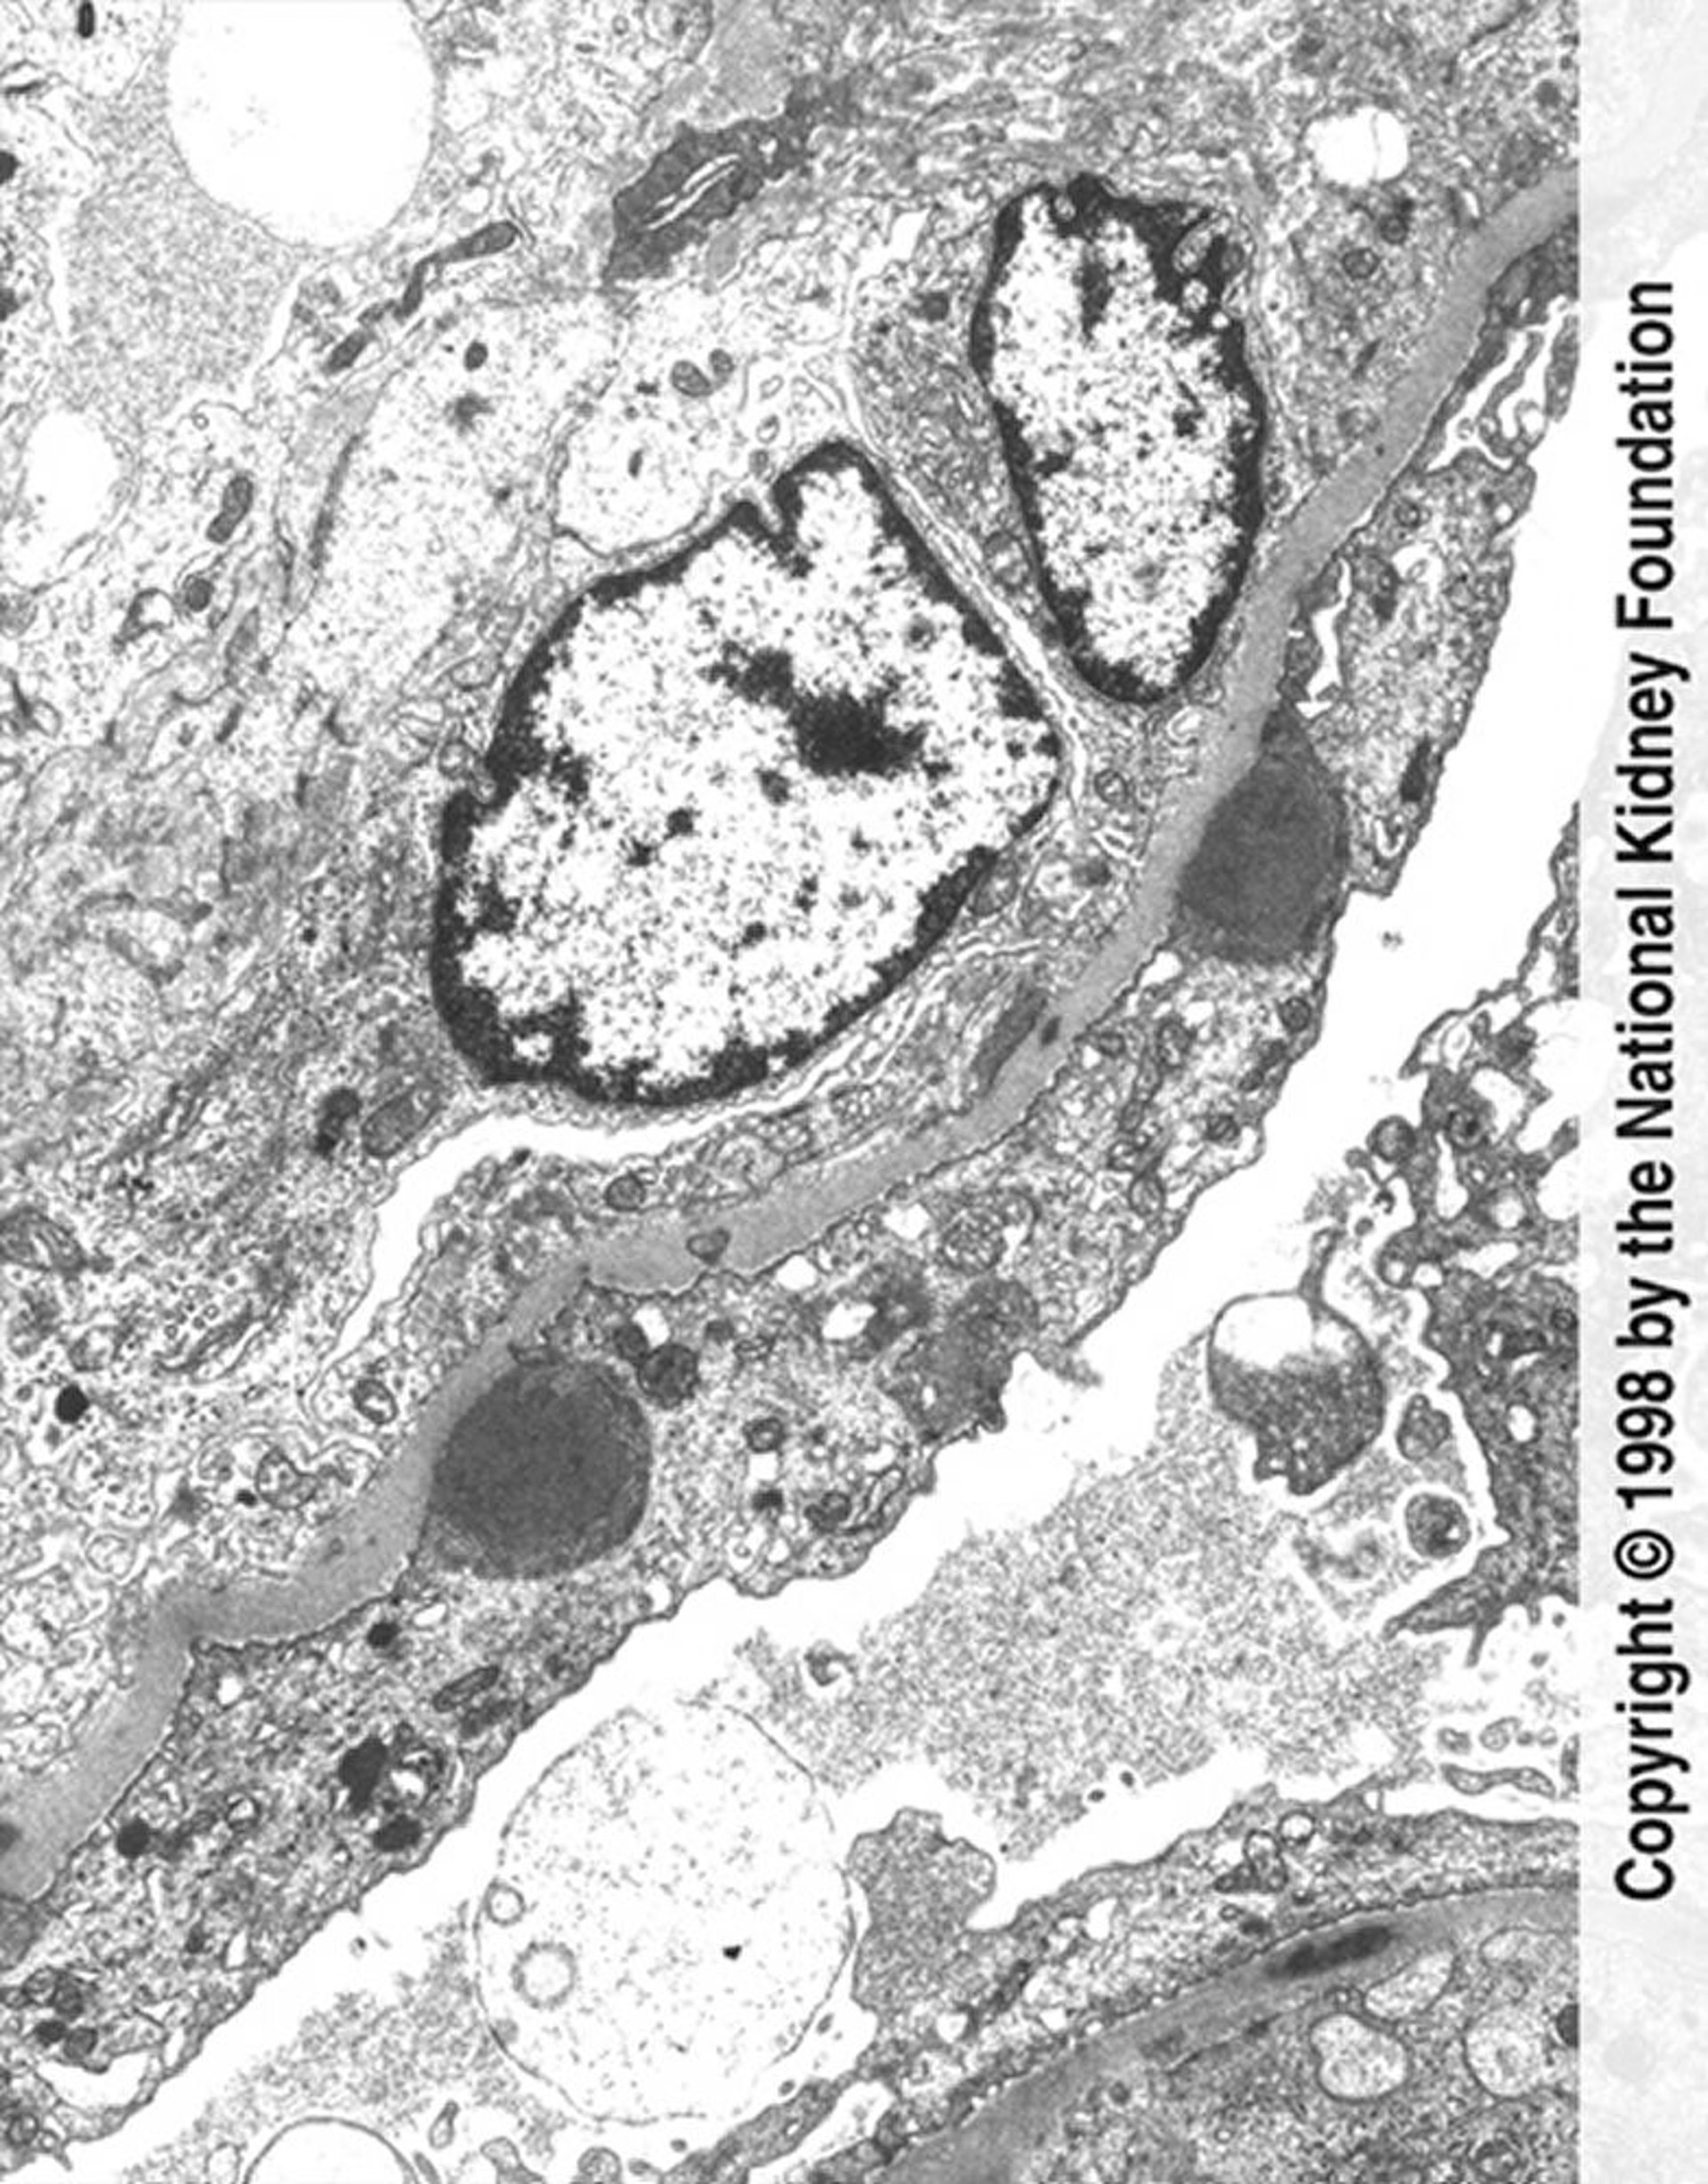

感染後糸球体腎炎(免疫複合体沈着)

広範な足突起の消失および管内増殖を伴うコブ状の免疫複合体沈着(暗灰色)が,透過型電子顕微鏡で示されている(11,250倍)。

Image provided by Agnes Fogo, MD, and the American Journal of Kidney Diseases' Atlas of Renal Pathology (see www.ajkd.org).